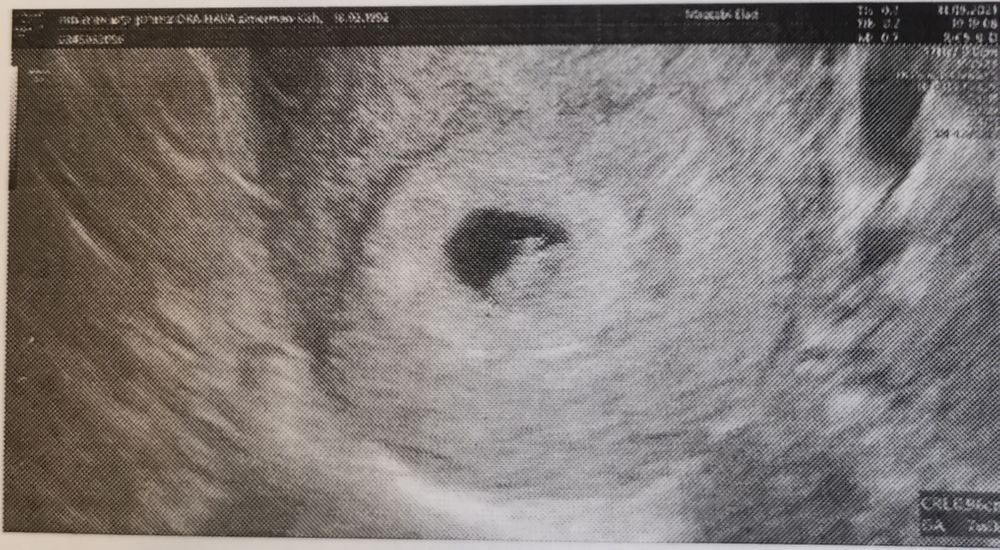

Первое узи бусинки